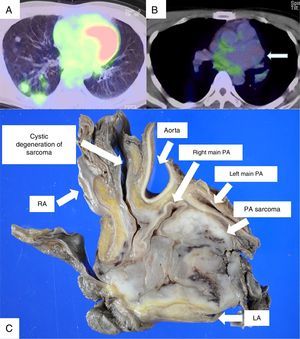

PET/CT showed FDG uptake in multiple lung nodules (A), but not in PA aneurysm (B). The thin arrow indicates PA aneurysm (B). Macroscopic findings from the specimen obtained by autopsy revealed PA leiomyosarcoma with cystic degeneration (C). PA, pulmonary artery; LA, left atrium; RA, right atrium.

A 38 year-old-man was referred to our hospital for right main PA aneurysm and well-defined multiple nodules in both lungs on chest CT. PET/CT showed FDG uptake in multiple lung nodules, but not in PA aneurysm (Fig. 1A and B). Transthoracic echocardiography and transesophageal echocardiography revealed PA aneurysm compressing left atrium. PA aneurysm due to PA sarcoma with multiple lung metastases was suspected, and the patient underwent thoracoscopic biopsy and pericardial fenestration. PA leiomyosarcoma was diagnosed on the basis of microscopic findings. Surgery was ruled out due to the prognosis and the invasiveness of surgical management. The patient received chemotherapy with pazopanib, which was stopped due to an allergic reaction with rash and fever. He was scheduled for second line chemotherapy, but died suddenly 2 months after the diagnosis. An autopsy was performed with the consent of his family about 26h after death.

The autopsy revealed main PA leiomyosarcoma with cystic degeneration (Fig. 1C) and multiple lung and myocardial metastasis. A large amount of blood was found in left thoracic cavity. Pathological findings were consistent with PA leiomyosarcoma with ruptured PA aneurysm. It was speculated that the cause of death was rupture of PA aneurysm.